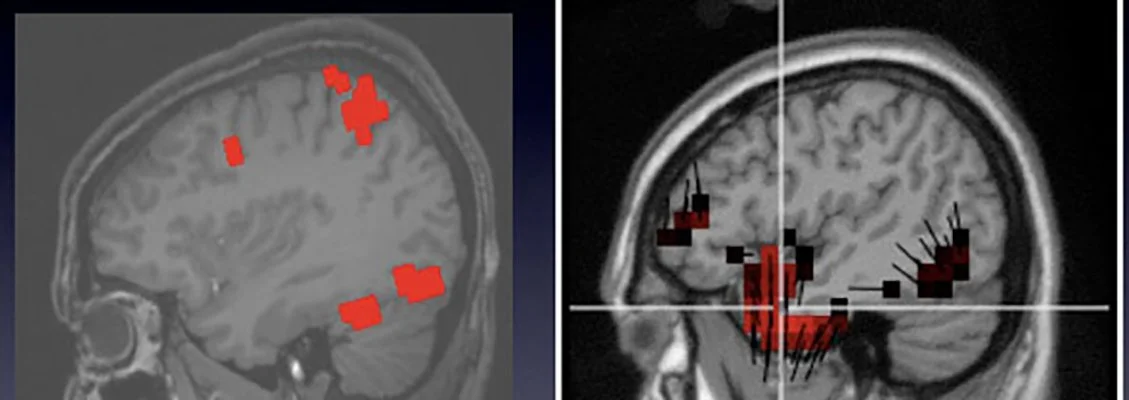

The results showed that dEEG measures were able to reveal the expert's visual response, even when satellite images were presented at rates (10/sec) that were too fast for the analyst to report targets consciously. This finding of brain target recognition was dependent on the ability to characterize the brain's response with millisecond time accuracy and localization of activity to specific brain regions, as shown in the several representations of the dEEG in this image.

An fMRI study of the unique neural responses to detecting targets (left image) showed that detection of military targets engaged not only visual areas (ventral temporal) but memory areas (posterior cingulate).  The corresponding dEEG source results (right image) are shown from activity at about 300 ms.  In general, the dEEG results showed similar activity in certain regions (including ventral temporal and posterior cingulate), but also showed greater activity in temporal areas than was seen by fMRI.

Whereas comparison with fMRI studies is essential to validate dEEG source results, hemodynamics and electrophysiology provide different views on brain activity, and and this difference remains poorly understood.